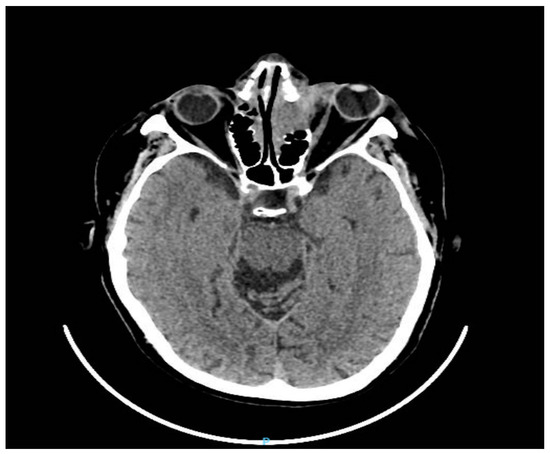

Standardized B-scan ultrasonography of the left eye did not reveal the presence of any intraocular mass. Computed tomography (CT) of the brain and orbit showed a front-ethmoid tissue mass with bone destruction and regional invasion (Figure 3).

Figure 3.

Computed tomography of the brain and orbit (axial planes) showed a front-ethmoid tissue mass with bone destruction and regional invasion with the left orbital extension in contact with the eyeball and left frontal intracranial extension of approximately 3.8/4/4.2 cm. The patient’s treatment began with maximal topical anti-glaucoma eye drops (topical beta-blockers, alpha-agonists, and carbonic anhydrase inhibitors). The patient’s care was subsequently co-managed with the oncological team. He started radiotherapy sessions according to the Intensity Modulated Radiation Therapy (IMRT)) scheme with a total dose of 30 Gy in 15 fractions given in 3 weeks and 2Gy/fraction. The irradiation was done with a thermoplastic mask after a CT planning where the tumor mass and adjacent structures were contoured (red color). Radiation doses delivered to normal anatomical structures (optic nerves, the lens) were within parameters (Figure 4).